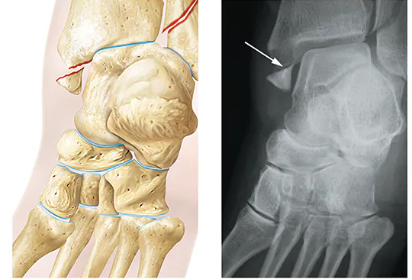

Avulsion